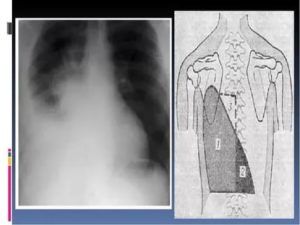

- Рентген. Проводится рентгенография в нескольких проекциях. Метод позволяет определить область поражения и характер процесса. На снимках патология проявляется затемнениями с размытыми контурами (на фото).

Плеврит легких на рентгенограмме